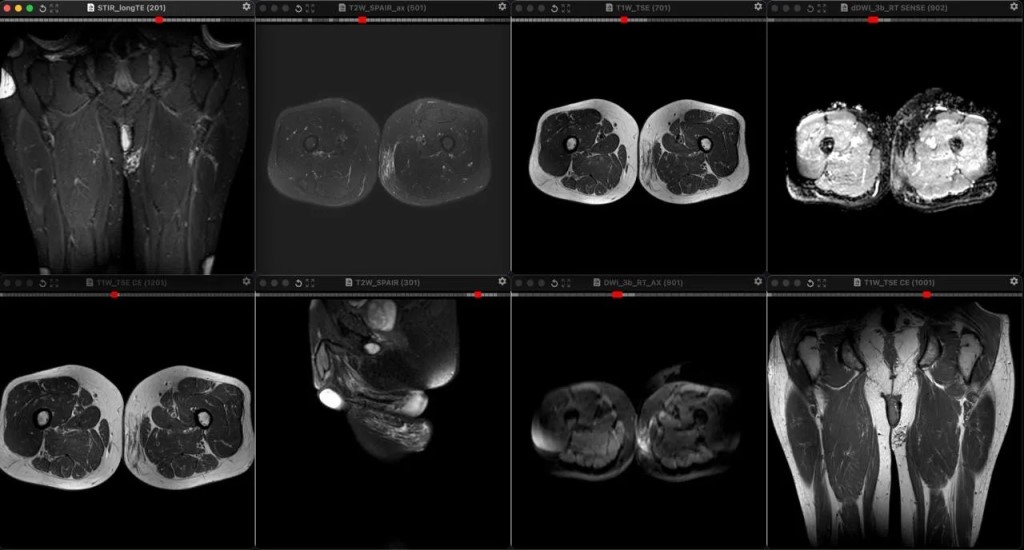

Фото Плексиформная кожная нейрофиброма у мужчины 34 лет с известным диагнозом Нейрофиброматоз первого типа. В отличие от типичных мишеневидных поражений, идущих вдоль крупных нервов при глубоких плексиформных нейрофибромах, поверхностные плексиформные нейрофибромы при НФ1, как правило, асимметричны, имеют немишеневидную структуру, не обладают узловатой или фасцикулярной морфологией и поражают кожу, а не только клетчатку. У этого пациента, как он говорит, шишка на внутренней поверхности левого бедра в течение многих лет, не меняется.